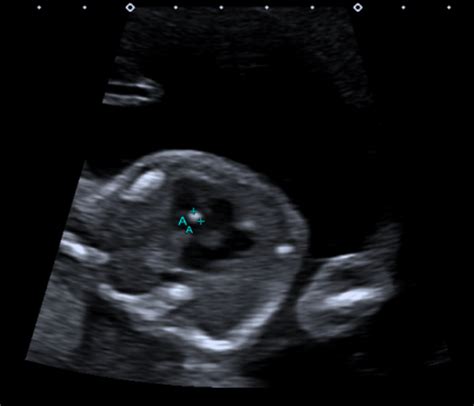

Let’s be real, guys, decoding medical jargon can feel like learning a new language! In the context of pregnancy forums and 20-week scans, OSCIPSEC is very likely a shorthand or a typo. It probably refers to the occipital-sphenoid complex (OSC) . This is a region at the base of the skull. If there’s concern about this area on a scan, it’s understandable to feel worried! The occipital-sphenoid complex is a crucial area during fetal development, and any potential issues flagged during the 20-week anatomy scan warrant careful evaluation. However, it’s important to remember that initial findings don’t always indicate a serious problem. Often, further investigation through additional imaging, like a more detailed ultrasound or fetal MRI, is necessary to get a clearer picture. These advanced imaging techniques can provide greater resolution and allow specialists to assess the OSC with more precision. The 20-week anatomy scan is designed to identify potential anomalies early on, giving healthcare providers the opportunity to monitor the pregnancy closely and plan for any necessary interventions after birth. While the waiting period for further evaluation can be stressful, remember that early detection is key to ensuring the best possible outcome for your baby. Your medical team will work diligently to gather all the information needed to provide you with an accurate diagnosis and a comprehensive management plan. So, try to stay positive and focus on taking care of yourself during this time. This includes getting plenty of rest, eating a healthy diet, and engaging in activities that help you relax and reduce stress.

The 20-week anatomy scan is super comprehensive, checking everything from the baby’s heart and brain to their little fingers and toes. It’s normal for something to pop up that needs a second look. Here’s the deal: even though it can be nerve-wracking, it doesn’t automatically mean something’s seriously wrong. Sometimes, it’s just that the baby was in a tricky position, or the image wasn’t crystal clear. A common finding is echogenic focus in the heart , which often resolves itself. Another one is mild ventriculomegaly (slightly enlarged fluid-filled spaces in the brain), which often needs monitoring but doesn’t always lead to problems. Also, keep in mind that variations in the size of certain structures , such as the kidneys, might be observed. These variations often fall within the spectrum of normal development but may warrant follow-up scans to ensure they resolve on their own. It’s also important to note that placenta position is routinely assessed. A low-lying placenta at this stage may require monitoring, as it could potentially lead to complications later in pregnancy. However, in many cases, the placenta migrates upwards as the uterus grows. Regardless of the specific finding, your doctor will explain the implications and recommend the appropriate course of action. This may include additional scans, consultations with specialists, or simply watchful waiting. Trust your medical team to guide you through the process and provide you with the best possible care. The key is to remain informed, ask questions, and focus on maintaining a healthy and positive mindset throughout your pregnancy. Remember, the vast majority of pregnancies result in healthy babies, and early detection of potential issues allows for timely intervention and improved outcomes.